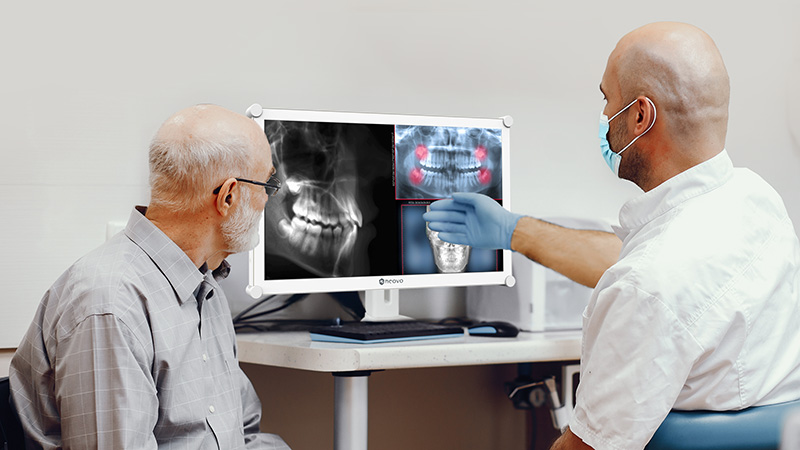

Tratamente Complexe

Consultații complexe, radiografii digitale și planuri de tratament personalizate.